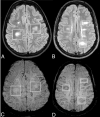

Background and purpose: Previous studies have suggested that the central vein sign and iron rims are specific features of MS lesions. Using 3T SWI, we aimed to compare the frequency of lesions with central veins and iron rims in patients with clinically isolated syndrome and MS-mimicking disorders and test their diagnostic value in predicting conversion from clinically isolated syndrome to MS.

Materials and methods: For each patient, we calculated the number of brain lesions with central veins and iron rims. We then identified a simple rule involving an absolute number of lesions with central veins and iron rims to predict conversion from clinically isolated syndrome to MS. Additionally, we tested the diagnostic performance of central veins and iron rims when combined with evidence of dissemination in space.

Results: We included 112 patients with clinically isolated syndrome and 35 patients with MS-mimicking conditions. At follow-up, 94 patients with clinically isolated syndrome developed MS according to the 2017 McDonald criteria. Patients with clinically isolated syndrome had a median of 2 central veins (range, 0-19), while the non-MS group had a median of 1 central vein (range, 0-6). Fifty-six percent of patients who developed MS had ≥1 iron rim, and none of the patients without MS had iron rims. The sensitivity and specificity of finding ≥3 central veins and/or ≥1 iron rim were 70% and 86%, respectively. In combination with evidence of dissemination in space, the 2 imaging markers had higher specificity than dissemination in space and positive findings of oligoclonal bands currently used to support the diagnosis of MS.